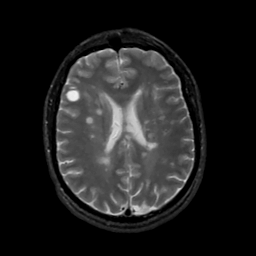

MR Study #2, February 17, 1991 -- Slice #31

[Home][Help][Clinical][Tour 1][Tour 2] Slice 31